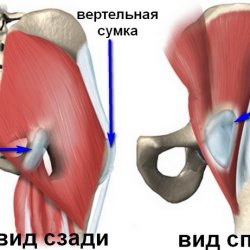

Здоровье суставов: Трохантерит и его влияние на мышцы